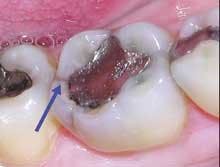

Under 3.5x or higher magnification, that peaceful row of gray-on-white may look more like a war zone. I use Class IV Orascoptic EyeMax loupes approximating a 5x view. This level of magnification took some getting used to, but now, little escapes me. In fact, I see things I never saw before. Where I previously saw old, but generally adequate alloy restorations, now I frequently discover minute coronal fractures subtly splitting a marginal ridge or areas of frank leakage that I previously missed (Figures 1 and 2). If you want to diagnose breakdown in progress, as opposed to waiting for inevitable failure, magnification is a must. It's one of several tools that give you more conviction when you make a diagnosis of pending failure. With more conviction comes greater confidence in your treatment plan. Your patients notice this and take your recommendations more seriously. Then, when you show them exactly why you believe their asymptomatic restoration is in jeopardy ... but now I'm jumping ahead of myself. Necessary as it is, magnification is just the first step.